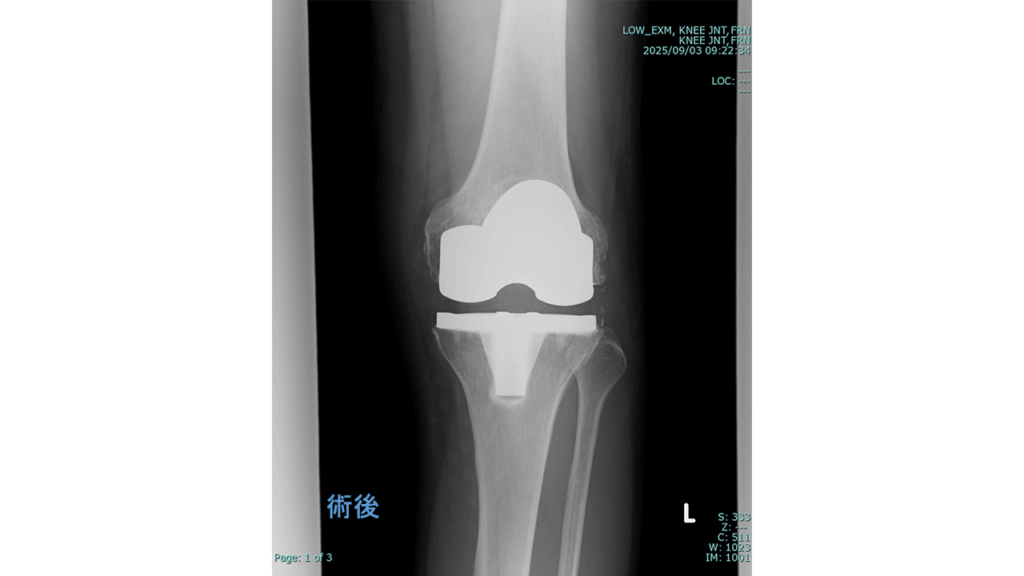

変形性膝関節症に対する手術

◆人工膝関節全置換術

(Total Knee Arthroplasty:TKA)

入院期間 3~4週間

外来リハビリ 2~3か月

術後